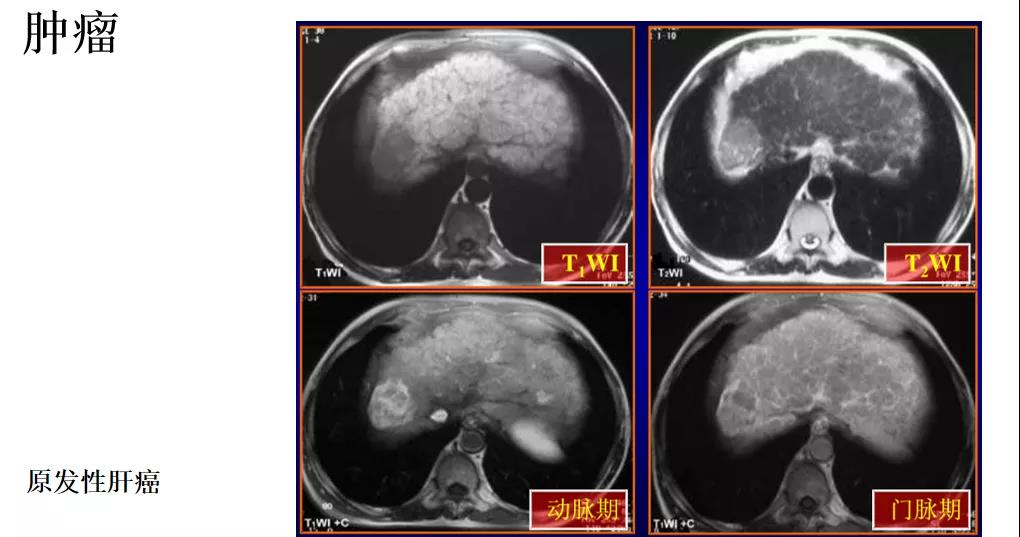

核磁共振成像能够对脑、心、肝等功能性反应进行精确的判定。在帕金森氏症、阿尔茨海默氏症、癌症等疾病的诊断方面,MRI技术都发挥了非常重要的作用。

讲座中,杨光钊博士根据多年影像学经验,并结合临床应用新成果。从核磁共振对不同症状人群的操作规范,到磁共振在人体各个组织系统成像后的影像分析,结合临床典型影像成片案例进行了多角度多层面的分享。杨光钊博士的悉心分享对我院磁共振的规范操作,及临床应用具有重要的指导意义。